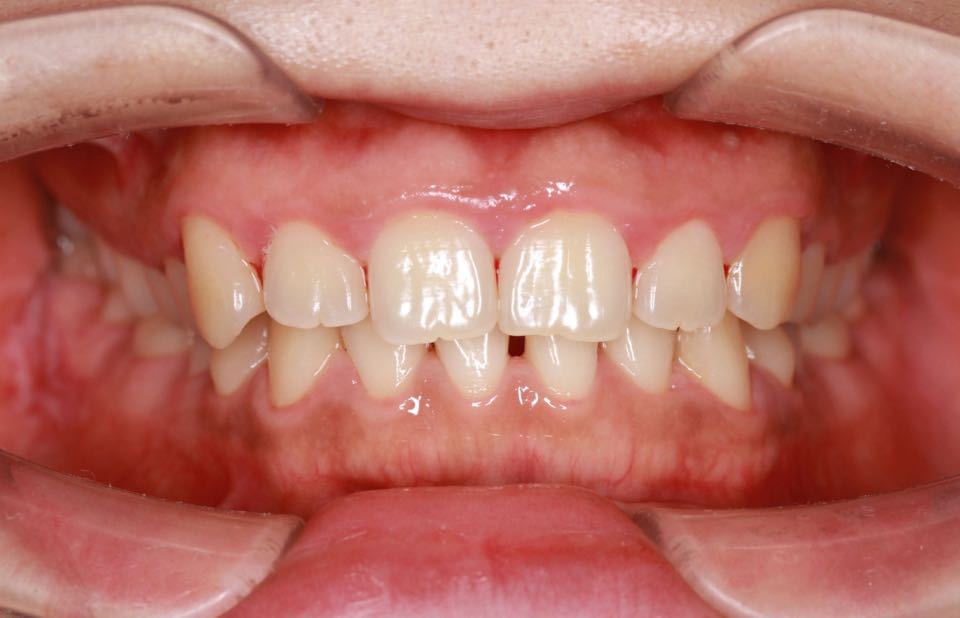

矫正前口内照:

正面观:面部左右基本对称,微笑正常。

口内:恒牙列,牙列拥挤(中度)。上下颌牙弓呈方圆型。左右对称。右侧磨牙近中性关系,左侧磨牙近中关系,右侧尖牙远中关系,左侧尖牙远牙中性关系。上颌中线偏右2mm,下中性居中。